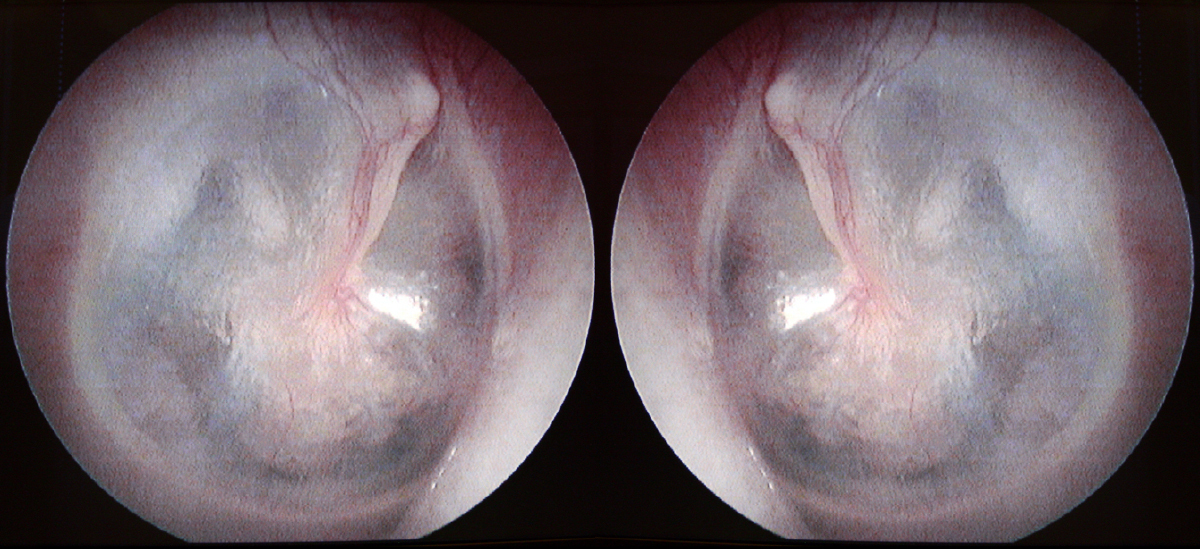

L’examen otoscopique est le suivant :

Il s’agit d’une otalgie à examen otologique normal : otalgie réflexe.